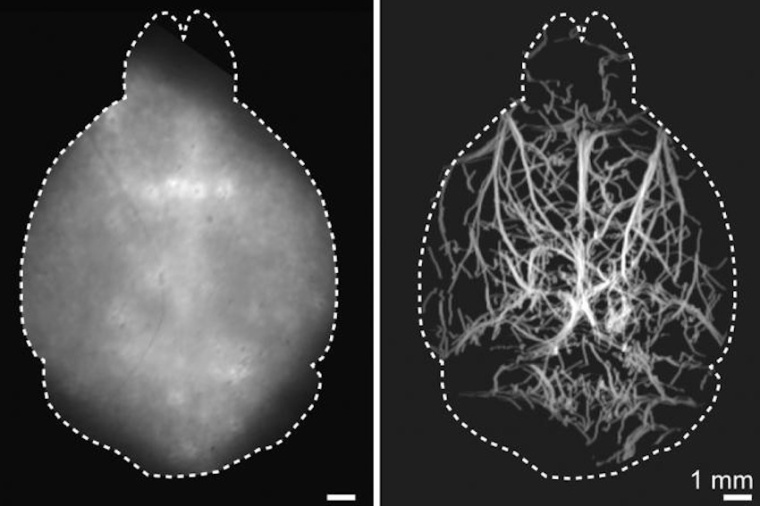

The researchers first tested the new technique in synthetic models of tissue that mimic average brain tissue properties, demonstrating that they could acquire microscopic resolution images at depths of up to 4 millimeters in optically opaque tissues. They then performed DOLI in living mice where cerebral microvasculature as well as blood flow velocity and direction could be visualized entirely noninvasively.

“Enabling high-resolution optical observations in deep living tissues represents a long-standing goal in the biomedical imaging field,” said Razansky. “DOLI's superb resolution for deep-tissue optical observations can provide functional insights into the brain, making it a promising platform for studying neural activity, microcirculation, neurovascular coupling and neurodegeneration.” For the new technique, the researchers intravenously inject a living mouse with fluorescent microdroplets at a concentration that creates a sparse distribution in the blood stream. Tracking these flowing targets enables reconstruction of a high-resolution map of the deep cerebral microvasculature in the mouse brain.